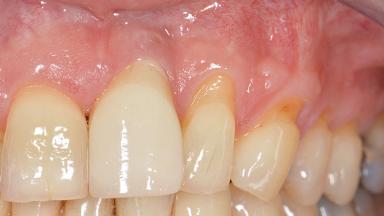

This case demonstrates that a connective-tissue graft in combination with a coronally positioned graft is an effective method of treating cases with peri-implant mucositis and an abutment-level sinus abscess. A 42-year-old man presented with a swelling adjacent to an implant crown at site 21. The swelling had been present for approximately three weeks and was constrained to the buccal and palatal gingival aspects of the implant. A discharge was noted on finger pressure, with localized gingival recession present on the mid- and distolabial aspects of the crown.